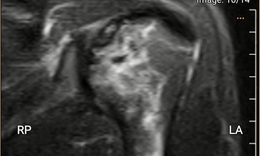

Cứu sống ngoạn mục cô gái 18 tuổi bị đa chấn thương do tai nạn giao thông

Y tế - 10/10/2025 16:23SKĐS - Sau tai nạn giao thông kinh hoàng, nữ sinh 18 tuổi được đưa vào Bệnh viện Đà Nẵng trong tình trạng nguy kịch, đa chấn thương, mất máu nhiều. Cuộc “chạy đua với tử thần” bắt đầu, các bác sĩ kích hoạt báo động đỏ, giành giật từng phút để giữ lại sự sống mong manh cho em.